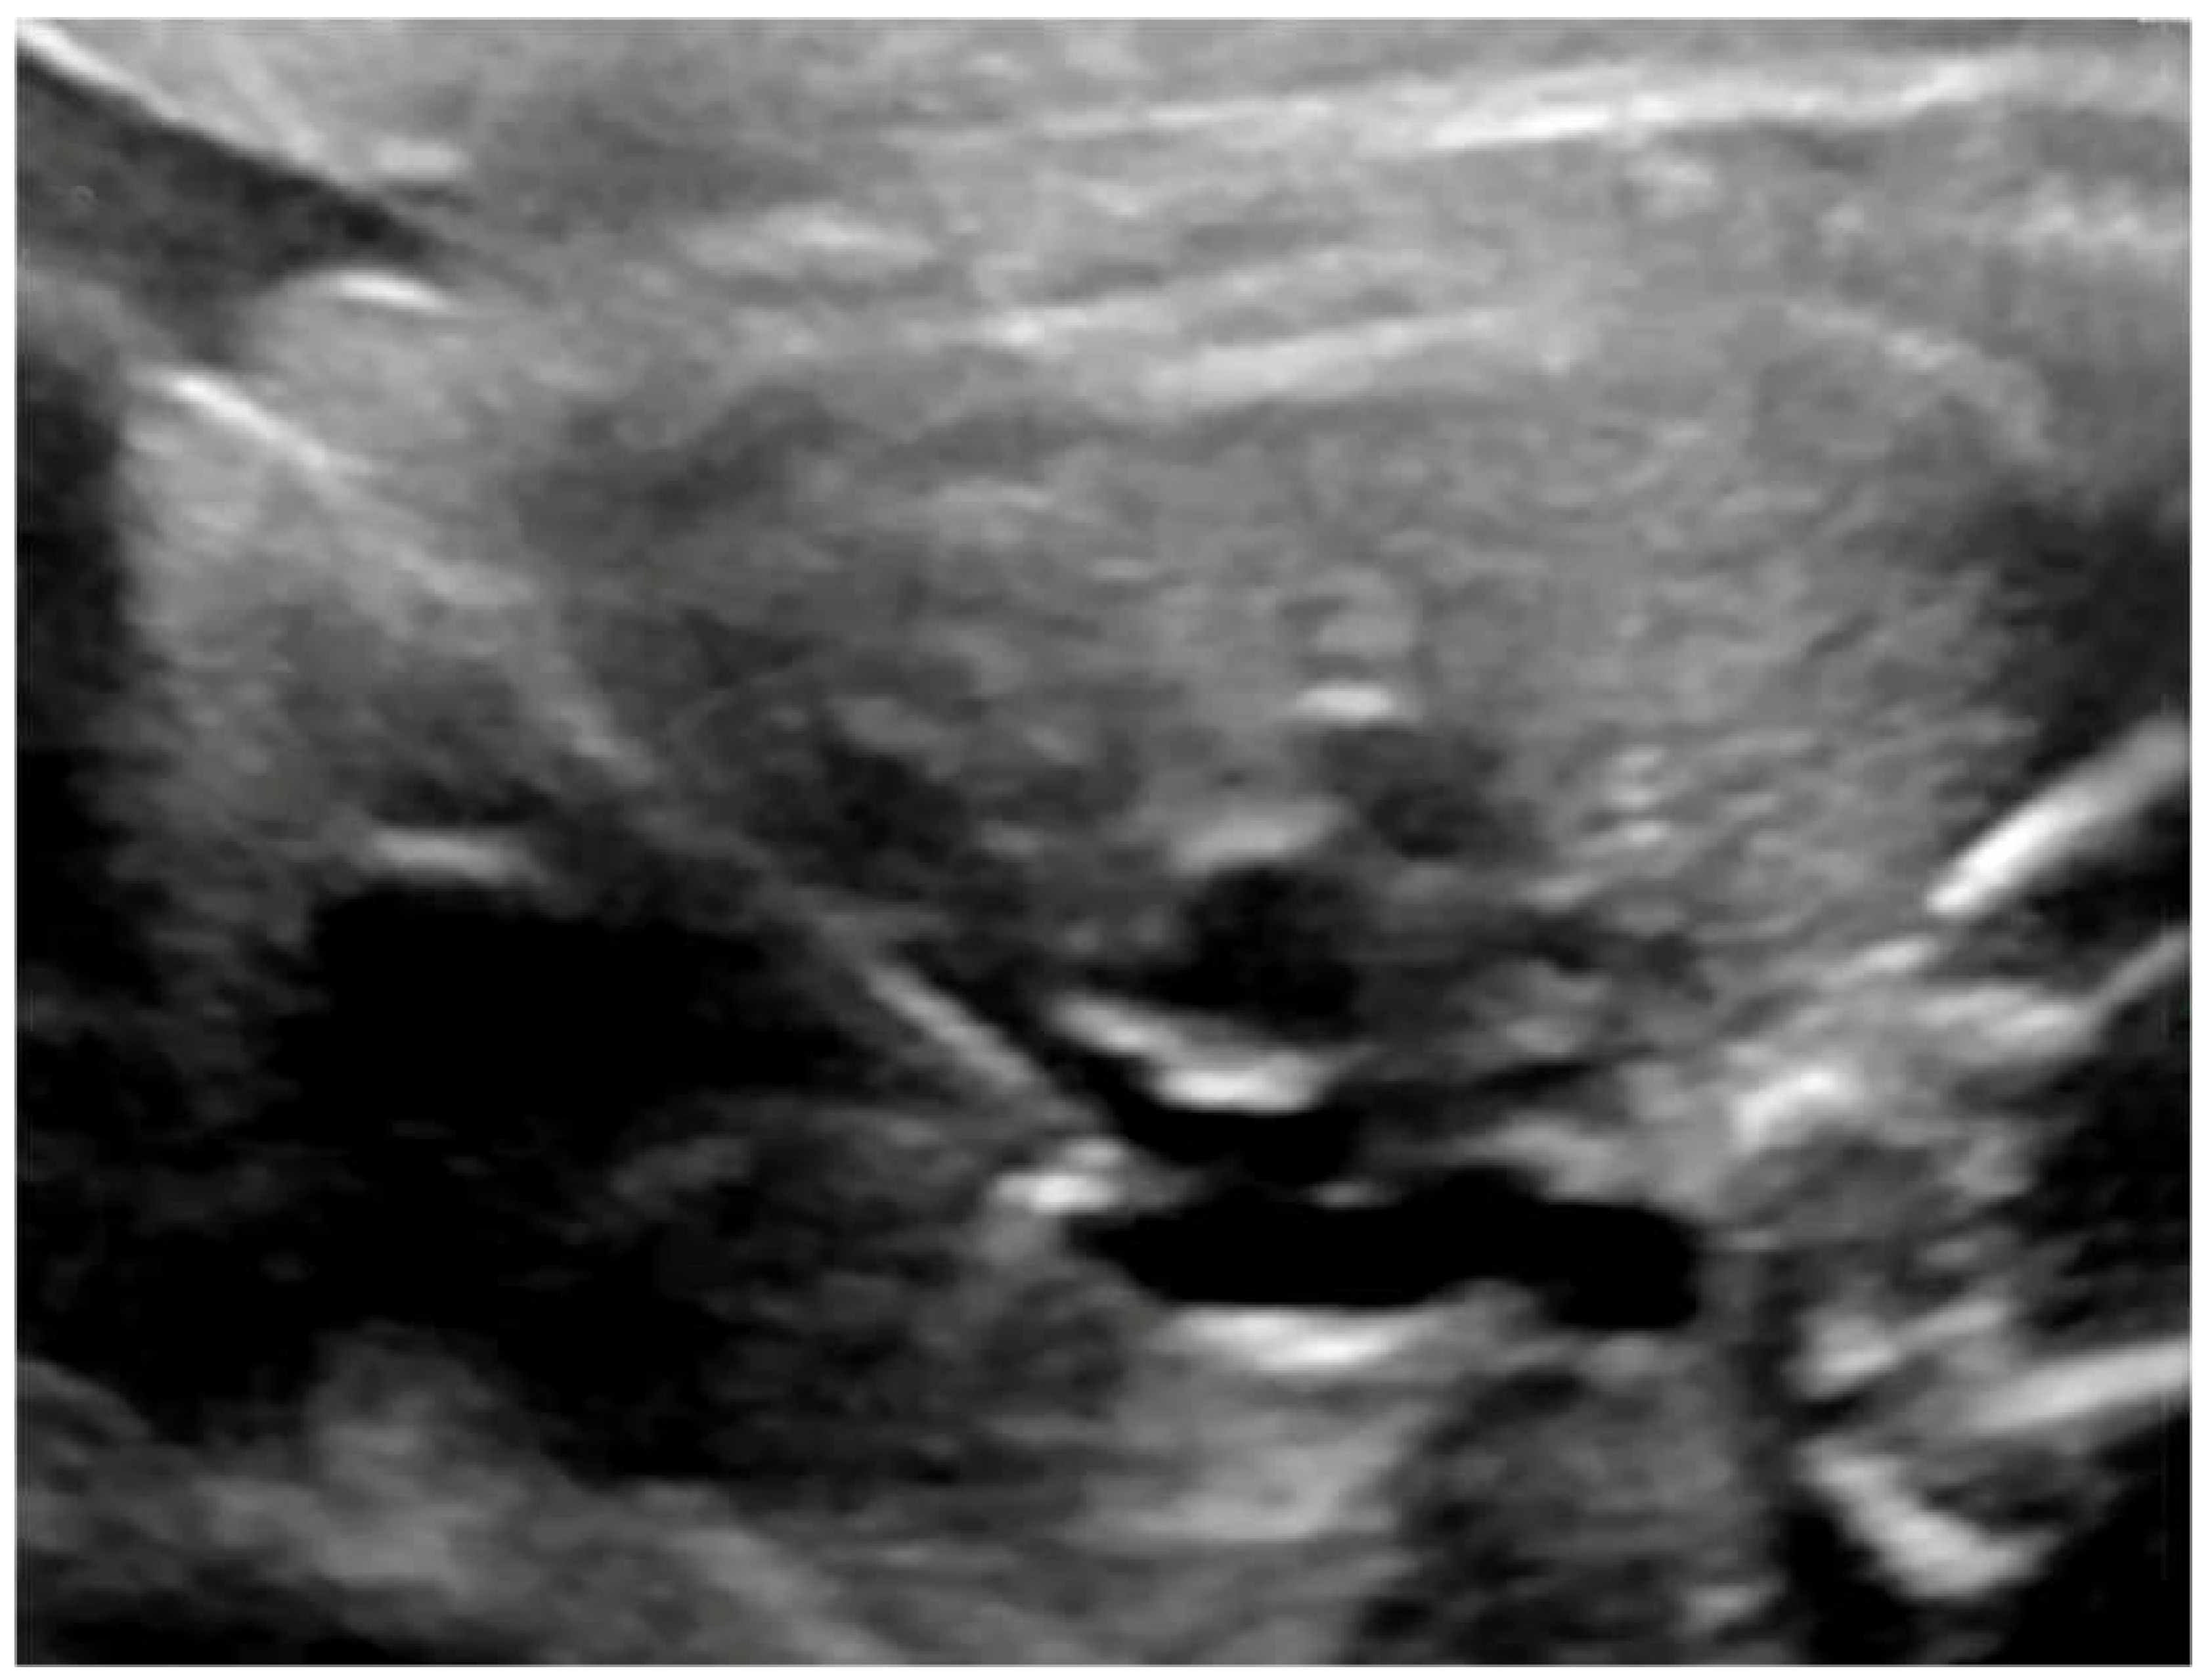

Fetal balloon pulmonary valvuloplasty (fBPV) was considered successful when the pulmonary valve was perforated with the needle and the guidewire with a balloon was introduced to the pulmonary trunk, the balloon was inflated and deflated at least three times, and the forward flow through the pulmonary valve was larger than before the procedure (Figure 5).

Figure 5.

fBPV—the guidewire was introduced through the needle and placed across the pulmonary valve.